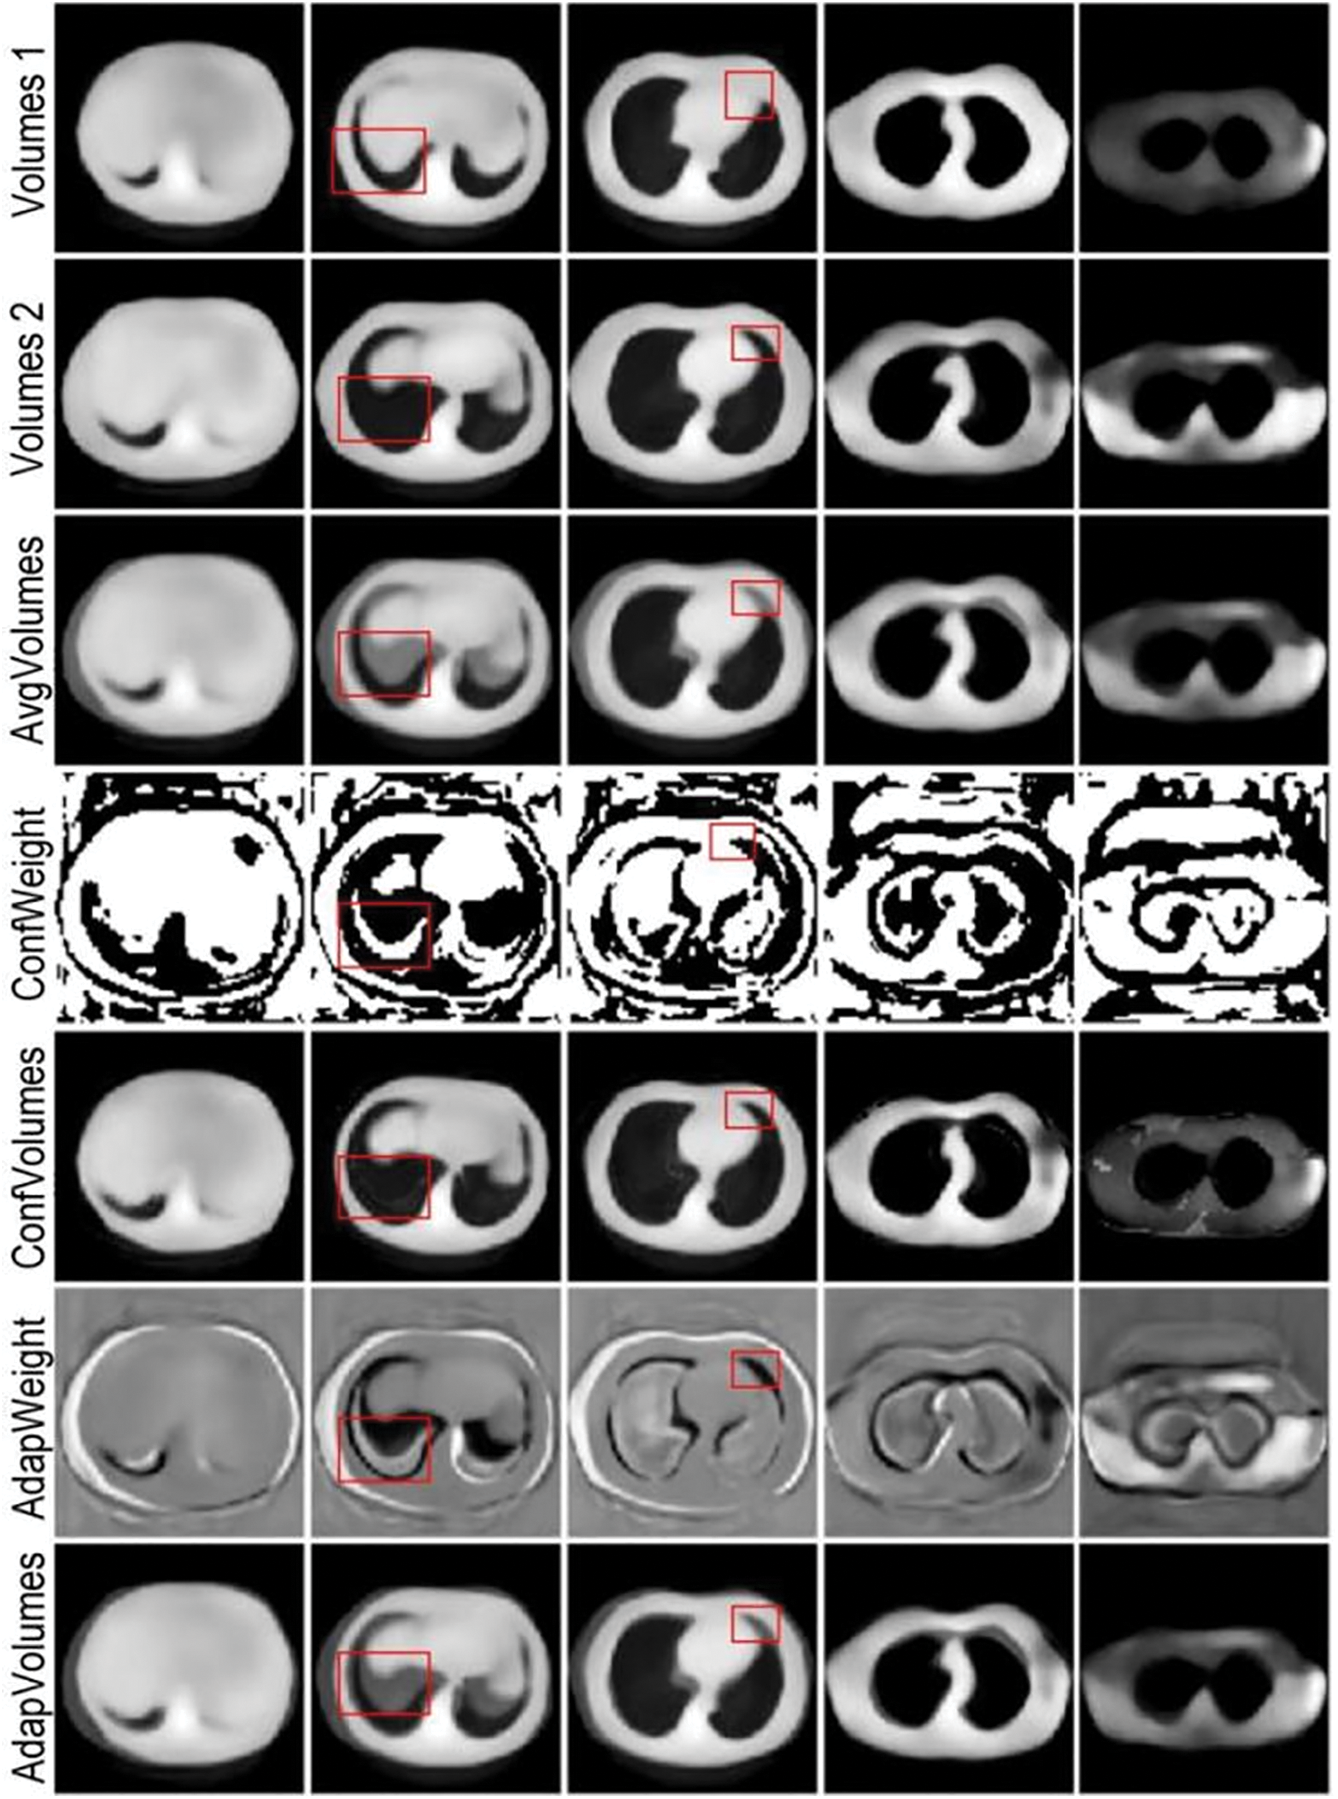

In terms of qualitative evaluation, the reasoning results of the four networks on the test samples are shown in Fig. 17. The experimental results show axial (horizontal) slices extracted from the reconstructed 3D volume at the same anatomical level as the source CT.

Figure 17: Qualitative evaluation of ablation experiments

The reconstruction result of SingleViewNet has obvious unreasonableness in the chest edge contour. Based on it, AvgFusionNet adds another sag as input, which improves the chest contour information, but there are still obvious deficiencies in the lung contour. After adding the adaptive fusion module to ConfFusionNet and AdapFusionNet, there are obvious improvements in both chest contour and lung contour reconstruction. The improvement of the reconstruction effect by the adaptive fusion module is very obvious in qualitative evaluation.

The edges of ConfFusionNet are very clear, and the grayscale is relatively consistent within the same tissue, but the noise is obvious. The contour of AdapFusionNet is relatively clear, but the grayscale distribution within the same tissue is somewhat uneven. Although the contour of this fusion method is not as clear as ConfFusionNet, it will not bring additional noise at the same time. In summary, AdapFusionNet is significantly better than SingleViewNet and AvgFusionNet in qualitative evaluation and has a slight advantage in quantitative evaluation.

In AdapFusionNet, with the aim of verifying the evaluation effect of the adaptive fusion module on the initial reconstruction results, the codec trained based on AdapFusionNet is used to experiment with different fusion methods. In AdapFusionNet and ConfFusionNet, the adaptive weight module generates the corresponding fusion weights adapweight1 and adapweight2 for the initial reconstructed voxels volumes1 and volumes2 of cor and sag and obtains the reconstructed voxels Adapvolumes based on adaptive weight fusion Adapfusion and Avgvolumes based on average fusion AvgFusionNet. Based on confidence value fusion, the reconstructed voxel Confvolumes with confidence weights confweight1 and confweight2 are fused. Multiple-slice examples are selected. The results of the experiment are shown in Fig. 18, where Adapweight and Confweight represent the weight of input volumes 1, and the sum of volumes 2 is 1, which is not displayed repeatedly.

Figure 18: Comparison of experimental results of multiple fusion methods based on adaptive fusion module